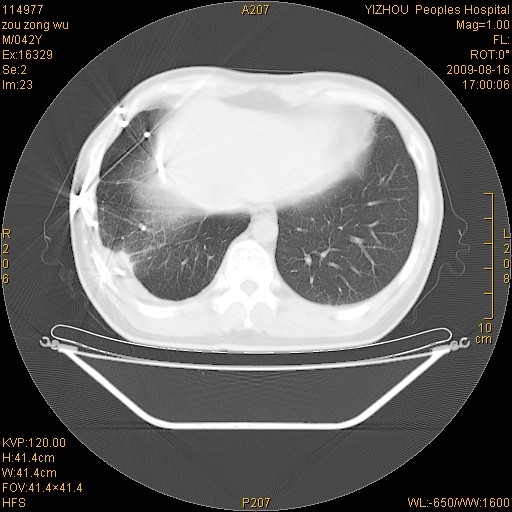

以下是引用zjzjr在2009-8-17 10:42:00的发言:[br]右侧间质性肺炎伴纤维化,右肺下叶肺囊肿伴感染(不除外外伤后引起),右肺野及胸壁软组织\\肝内见多发斑点状,中枪了吧.右侧胸膜肥厚\\粘连.